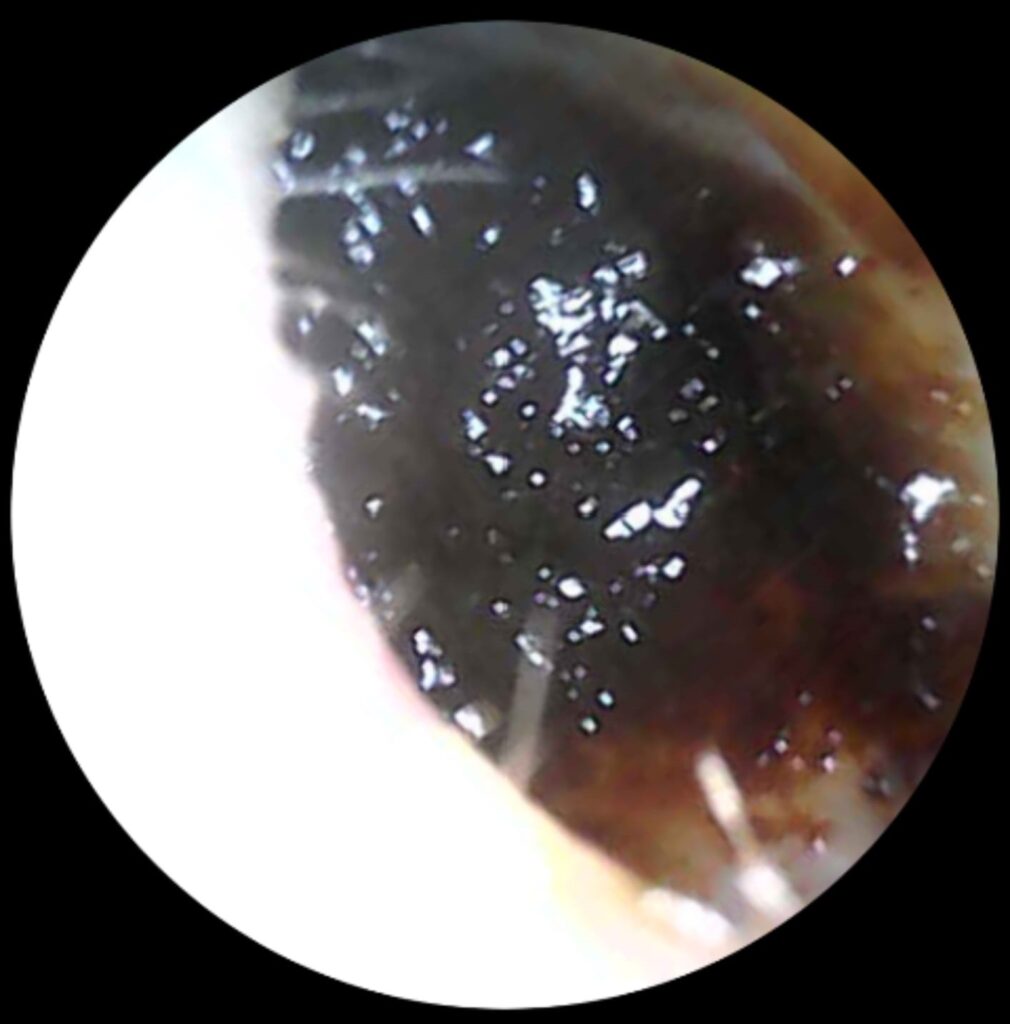

Do your ears feel “full,” muffled, or even a little itchy? You might be dealing with blocked ears; a common problem caused by earwax buildup. While it’s usually harmless, blocked ears can be uncomfortable, affect your hearing, and sometimes even cause ringing or dizziness. The good news? Professional earwax removal is safe, quick, and can make your ears feel like new again.

Why You Shouldn’t Try to Fix It Yourself

Blocked ears are more common than you think — but they don’t have to affect your daily life. Professional earwax removal can restore your hearing, comfort, and confidence.